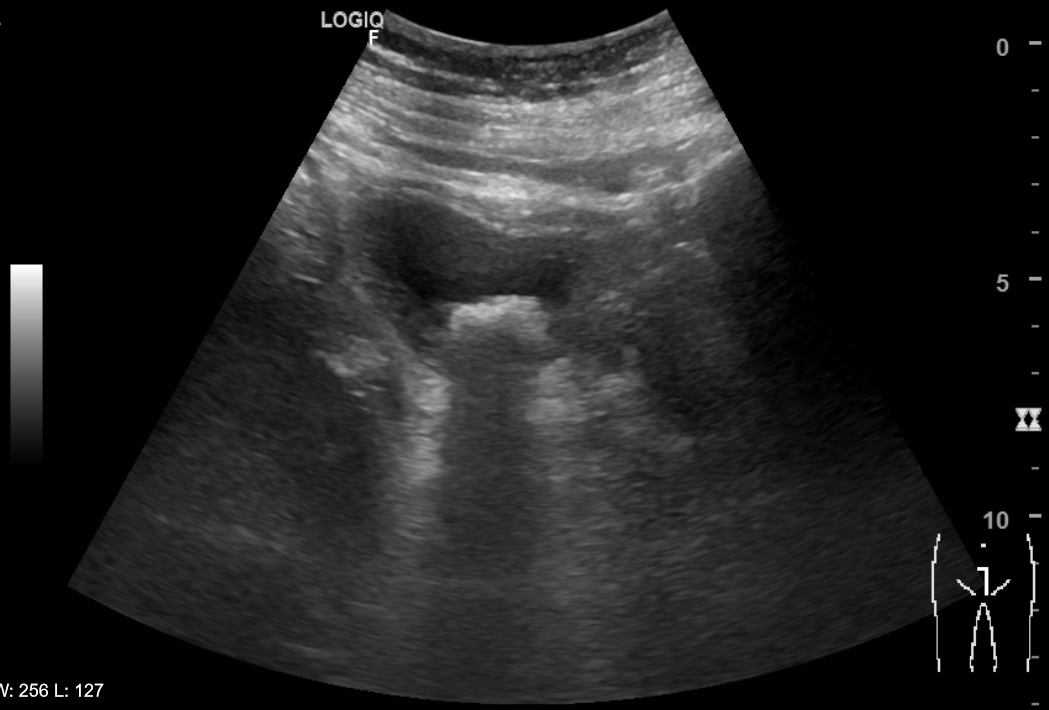

Riñones de morfología y tamaño normales. No se aprecian colecciones intrarrenales ni perirrenales. Sin ectasia de sistemas excretores. Quiste cortical simple en polo superior de riñón izquierdo de 6x6cm. Vejiga poco replecionada de paredes uniformemente engrosadas y trabeculadas. Múltiples imágenes hiperecogénicas con ausencia de registro Doppler y con sombra posterior que sugiere cistolitiasis. Próstata de aspecto normal con volumen de 21 cc. Volumen premiccional de 89 cc y posmiccional de 11 cc.